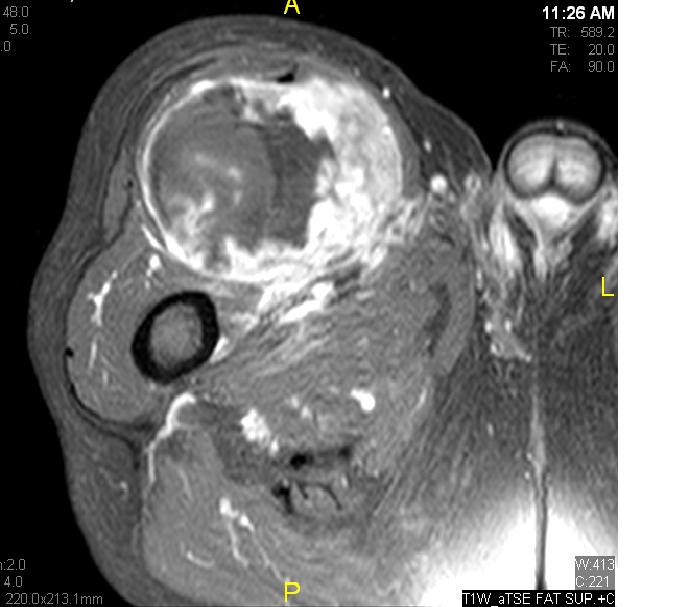

• Large encapsulated lipomatous mass with multiple thick internal trabeculations. (Fig. 1 – 13)

• Signal loss on FS T1 weighted images, and focal nodules(>1 cm is suggestive of a DDLS). (Fig. 1 & 7)

• Contrasted images show hyper-enhancement of the tumors. (Fig. 4, 5, 11-13)

Fig. 7 & 8 Magnetic Resonance Image shows a large heterogeneous mass in the right thigh with low intensity signal on Axial (Fig. 7) and Coronal (Fig. 8) T1-weighted images admixed with high signal areas. The high signal areas represent low grade fatty tissue and low signal the dedifferentiated areas. Higher intensity signal is visible compatible with hemorrhage or necrotic tissue.

Fig. 11 – 13 Axial (Fig. 11), Coronal (Fig. 12) and Sagital (Fig. 13) contrasted T1-weighted MR images show a large heterogeneous mass with central and peripheral

enhancement. Multiple thick trabeculations. Central low signal intensity image is compatible with necrosis and hemorrhage.